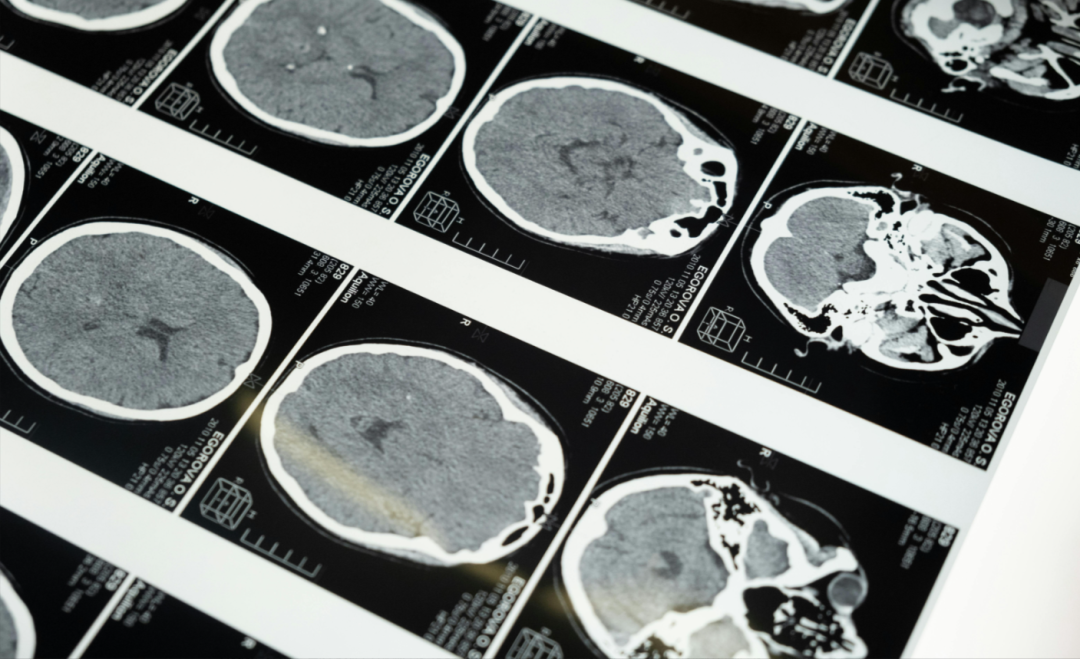

人脑的衰老速度与认知衰退、神经退行性疾病风险密切相关。然而,传统脑龄(Brain Age,BA)模型仅能反映从出生到检测时间点的累积衰老效应,无法捕捉近期或动态的衰老速率。

这一问题在阿尔茨海默病(AD)等神经退行性病变的早期预警中尤为突出。现有基于血液 DNA 甲基化的衰老速度(Pace of Aging,P)检测方法因血脑屏障的存在难以准确反映神经组织的真实衰老状态。

为此,南加州大学(University of Southern California)的研究团队开发了一种基于纵向 MRI 和三维卷积神经网络(3D-CNN)的纵向模型(Longitudinal Model,LM),首次实现了大脑衰老速度的非侵入式精准量化,并通过显著性映射技术揭示了衰老速率的解剖学特征差异。